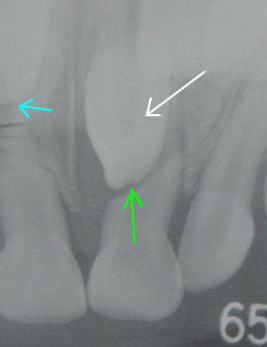

4歳頃に、乳歯がぐらぐらしてきたと相談を受けることがあります。過去に歯を打った場合も,早く歯がぐらついてくることがありますが,その他に過剰歯といって,余分な歯がありそれが乳歯の根を吸収し,ぐらついてくることもあります。左の写真の白い矢印の歯が過剰歯です。ブルーの矢印は,正常な乳歯の根の先ですが,緑の矢印は吸収された根の先です。これは下から伸びてきた過剰歯によって,根が吸収されてしまったものです。根が短くなりぐらぐらしてくるのです。永久歯の歯並びに悪い影響があるようなら,乳歯も過剰歯も抜歯することもありますが、どのような治療になるかはその状況により違いがあります。主治医とよく相談の上、対処されることをお勧めします。